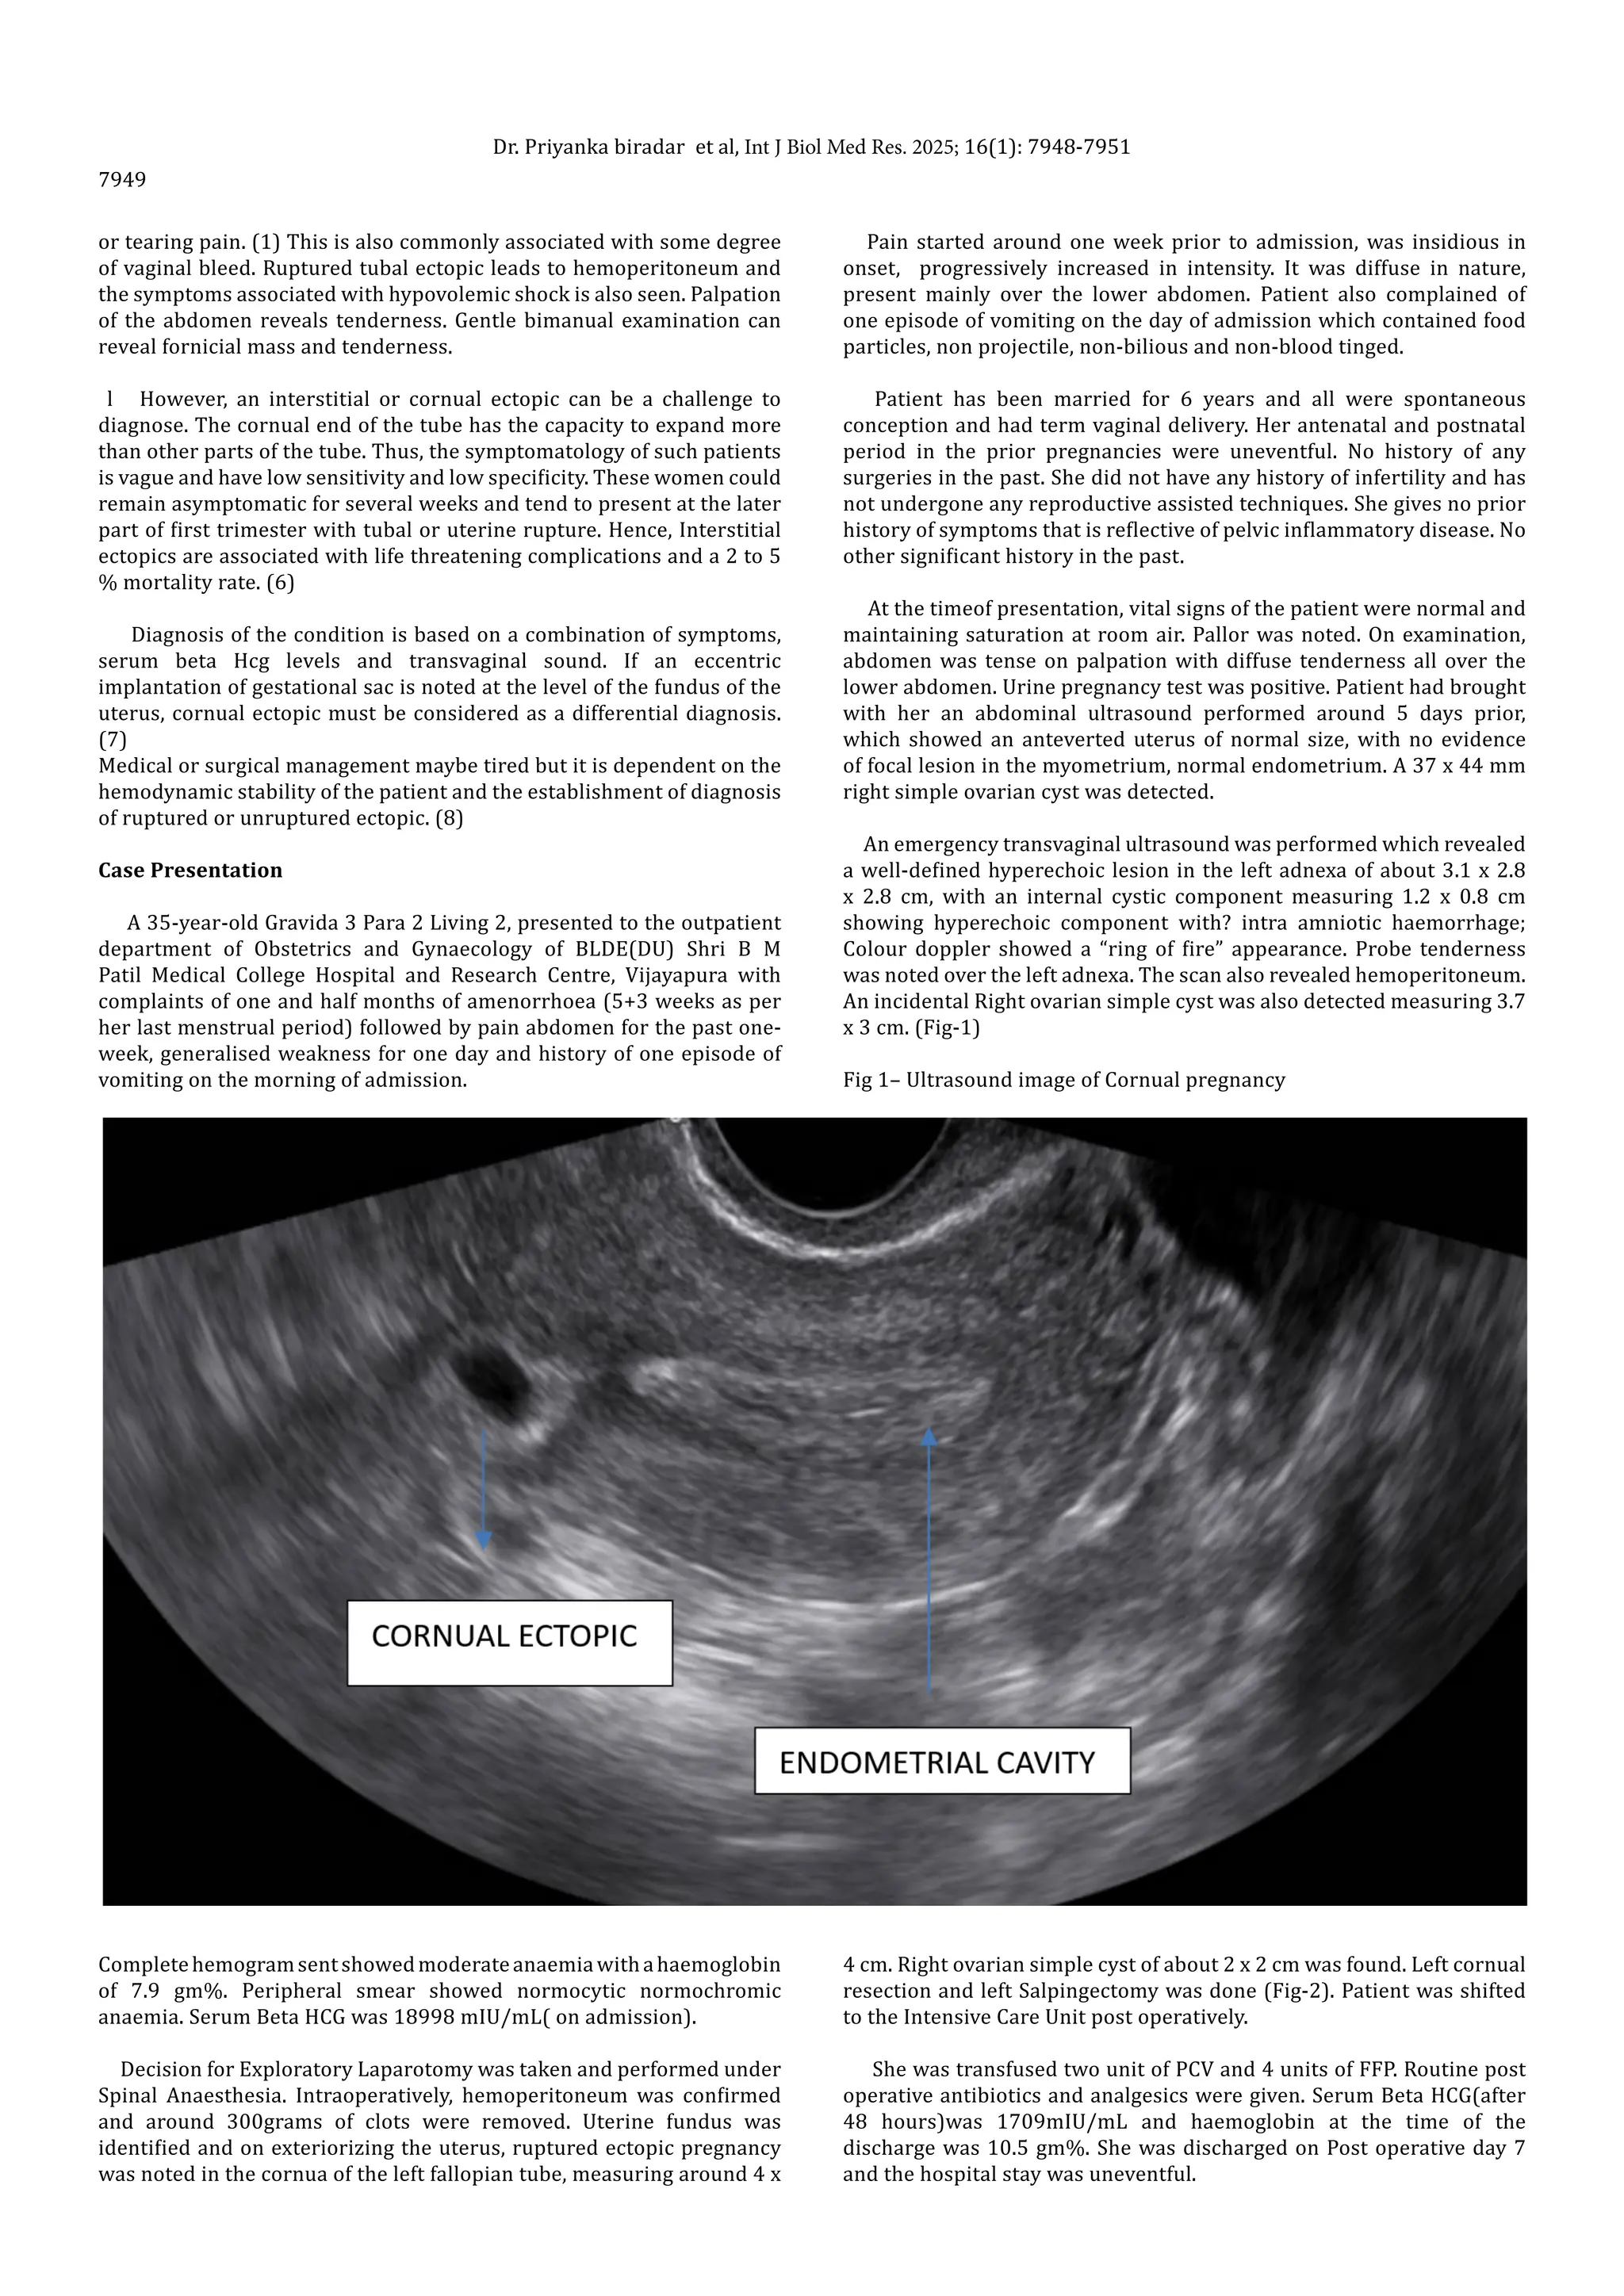

Learn about the diagnosis, risks, and treatment options for cornual interstitial pregnancy. Discover why this rare ectopic pregnancy requires urgent medical intervention to prevent rupture. Understand the symptoms, surgical management techniques like laparoscopic resection, and maternal health implications associated with this life-threatening condition in our comprehensive medical guide designed for patients and healthcare providers seeking accurate, expert information.

Read full article: Cornual Interstitial Pregnancy